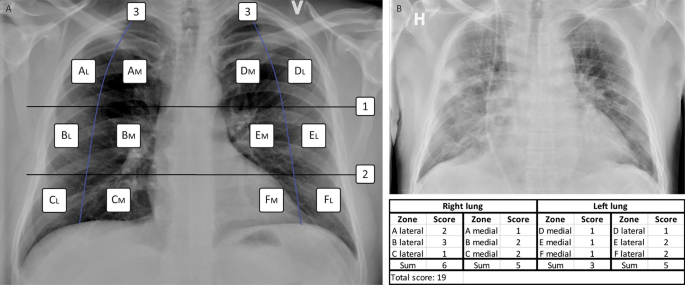

As defined in the Brixia score10, CXR images in the posteroanterior or anteroposterior projection had each lung divided into three zones, by two horizontal lines: one inferior to the aortic arch and one inferior to the hilar structures. Each zone was then further divided into additional medial and lateral subzones: i.e. medial A, and lateral A; medial B, and lateral B; medial C, and lateral C; medial D, and lateral D; medial E, and lateral E; medial F, and lateral F, by drawing vertical lines from the pulmonary apices to the middle of the diaphragm on each lung. Each vertical line was curved to match the curvature of the ribcage. The resulting 12 individual zones, six in each lung, were scored according to the severity of the lung lesions using a score from zero to three per zone. (Fig. 1).

(A) The MBrixia scoring system. Box 1 and 2 mark the horizontal division corresponding to the inferior wall of the aortic wall, and the inferior wall of the right pulmonary vein, respectively, creating three zones in each lung: A, B, C, D, E and F. Box 3 marks the vertical line drawn from the pulmonary apices to the diaphragm, creating further division into medial (M) and lateral (L) zones. (B) A clinical example of a chest x-ray image scored using the MBrixia score.

A score of zero was given if no lung lesions were present in the respective zone, a score of one if interstitial infiltrates were present, a score of two if both interstitial and alveolar infiltrates were present, and a score of three if consolidations were present. In order to divide the findings more clearly, the definition of a score of three was altered from interstitial and alveolar infiltrates with alveolar predominance, as defined in the Brixia scoring system, to consolidations. Each zone was scored according to the most dominant pattern in the respective zone. CXR images of patients suffering from subcutaneous emphysema were assigned the same score as the CXR image scored prior to CXR-verified subcutaneous emphysema. Scores from all 12 zones were summarized into a final score ranging from zero to 36.